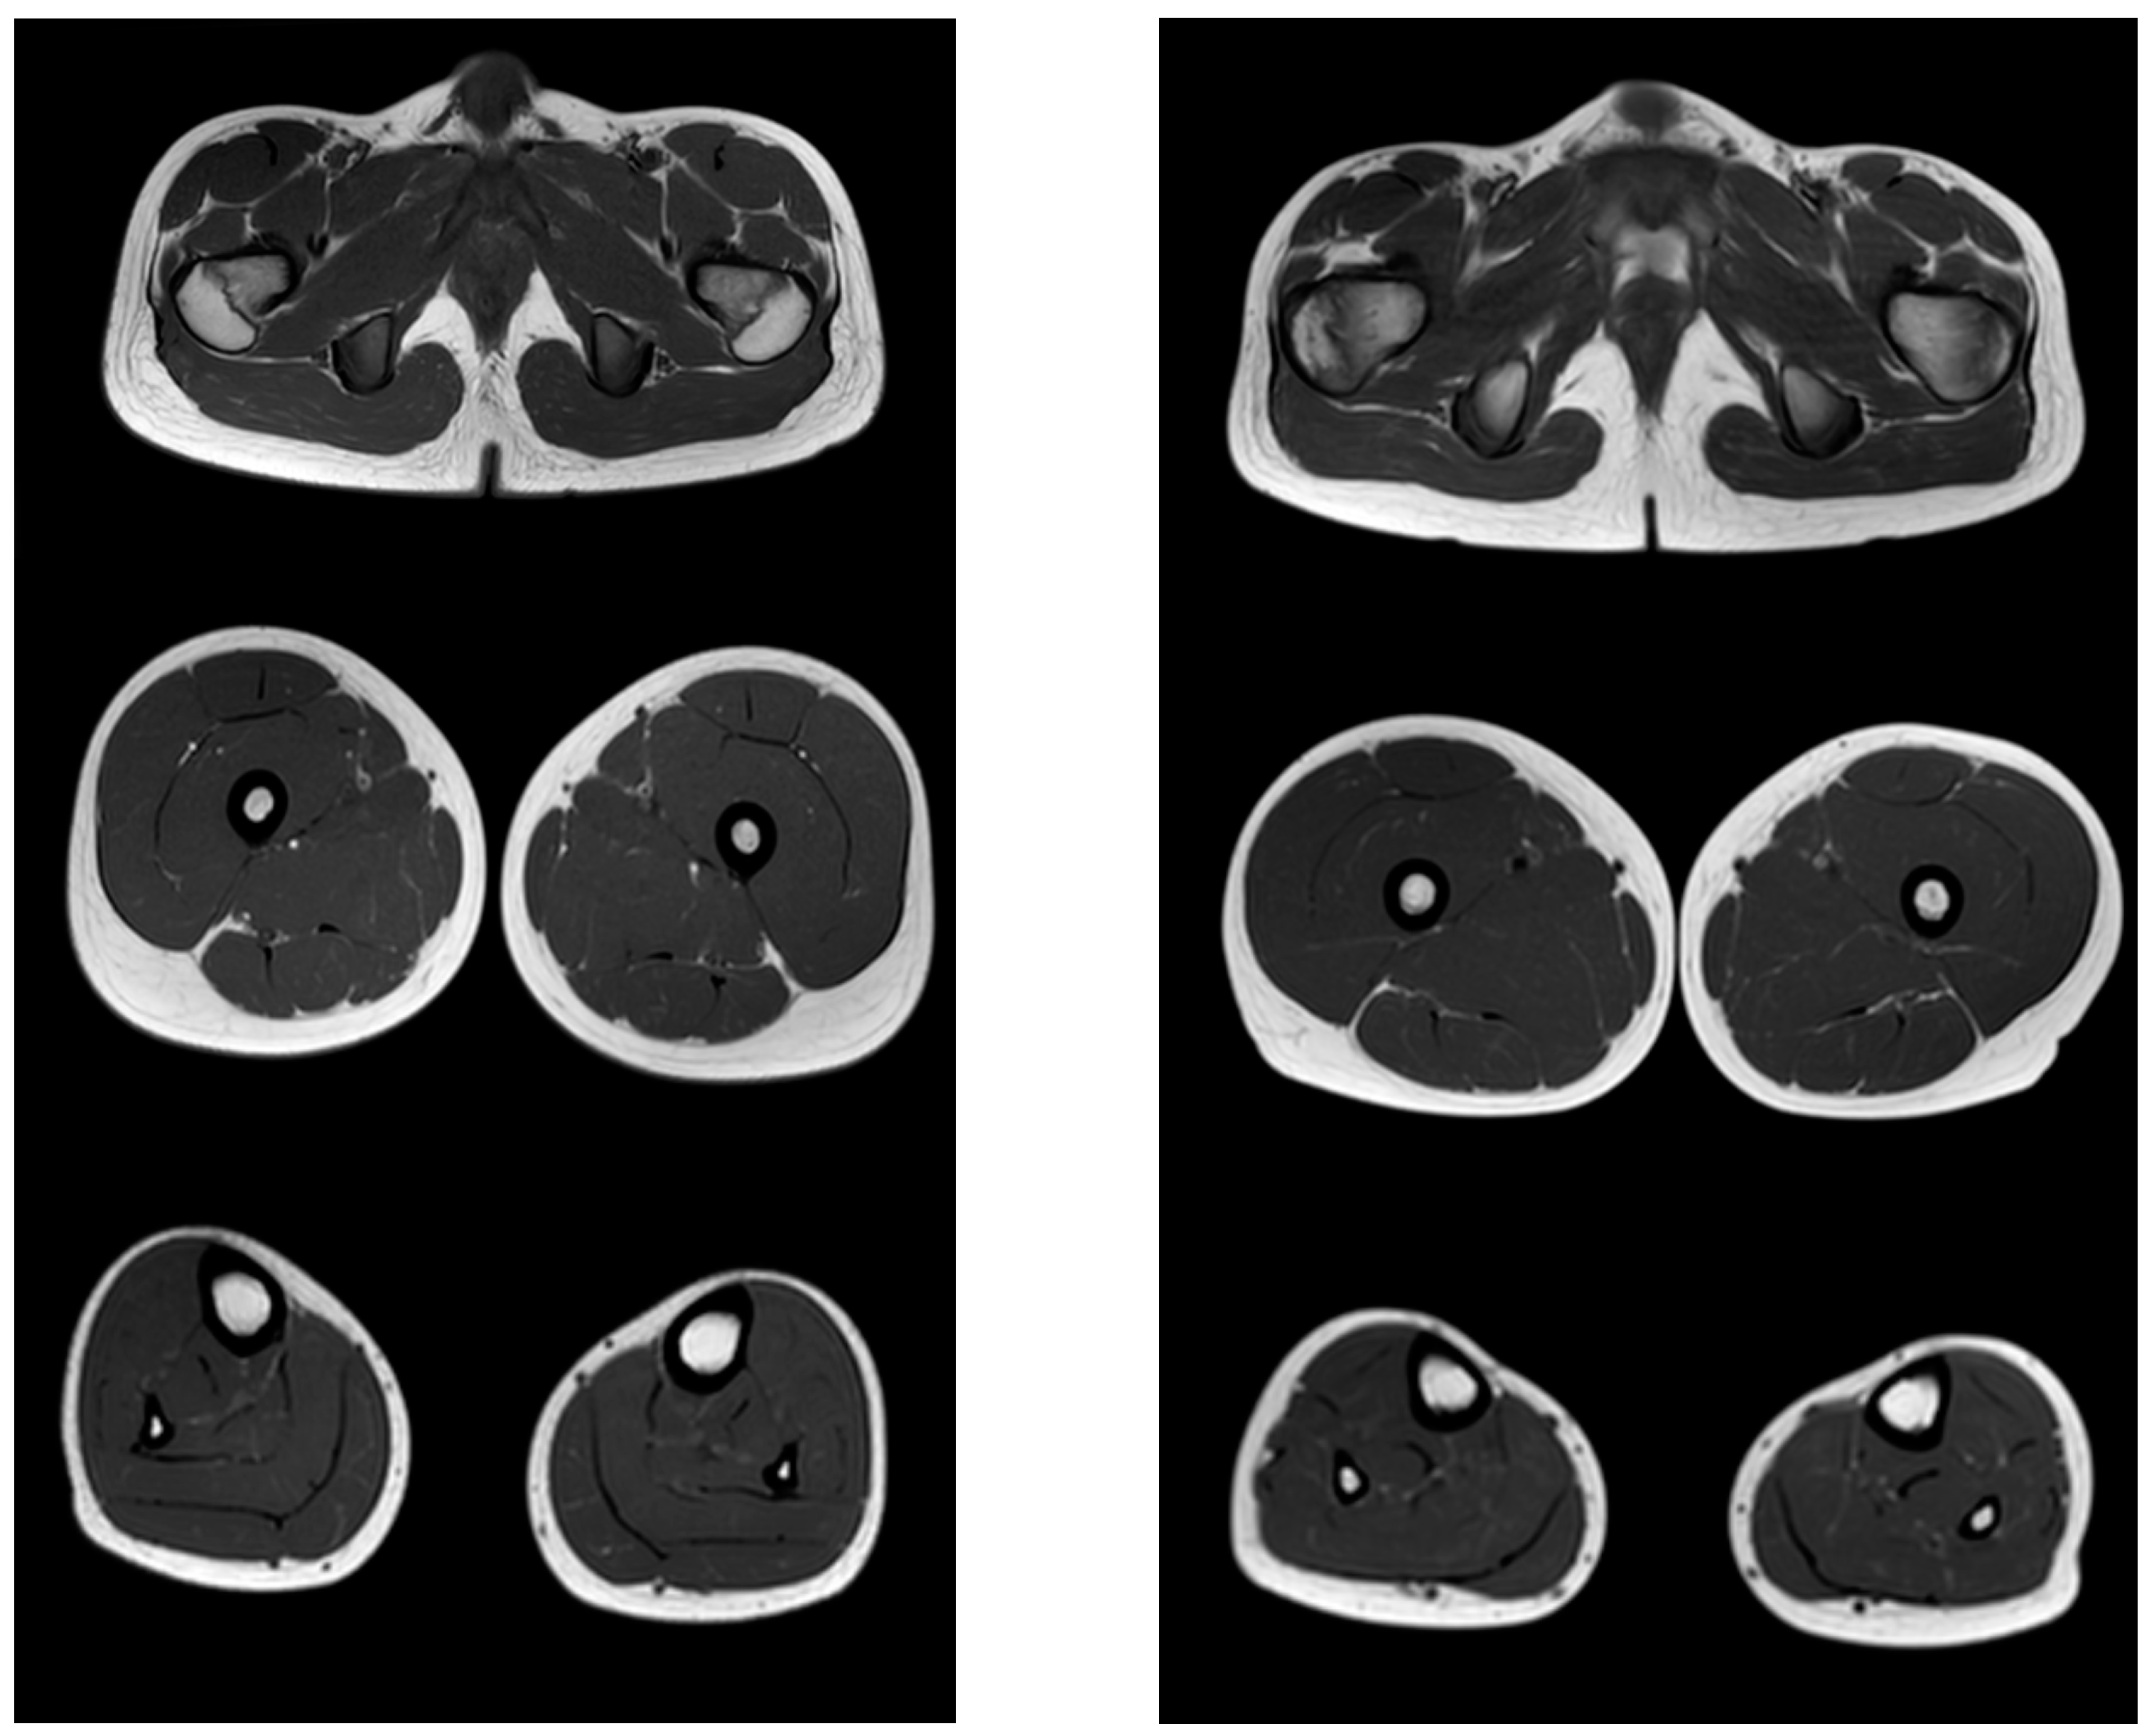

Figure 3, Figure 4 and Figure 5 show the main changes in the muscles at different stages of the disease. The muscles of the pelvic girdle are characterized by early symmetric fibro-fatty degeneration of the gluteus maximus muscles, in the Figure characterized by stage 2b on the Mercuri scale. In the hips, the early lesion pattern is characterized by primary involvement of the adductor mausors (stage 2a). It is also characterized by slight diffuse changes in the quadriceps muscles and the posterior group of muscles of the thighs. In the muscles of the legs at the early outpatient stage, nonspecific diffuse muscle fat substitution is characteristic of stage 1 (Figure 3).

Figure 3.

Pattern of involvement of the muscles of the lower extremities in a patient at an early outpatient stage of the disease (6.1 years). From top to bottom: the pelvic level, the femoral level, and the level of the legs.